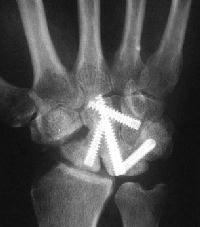

styloid bone graft, and the distal pole was excised. Postoperatively, carpal instability was present.

This progressed...

Carpal tunnel developed and progressively worsened, probably related to the palmar prominence of the lunate. The patient underwent carpal

tunnel release and midcarpal fusion and returned to heavy manual work.